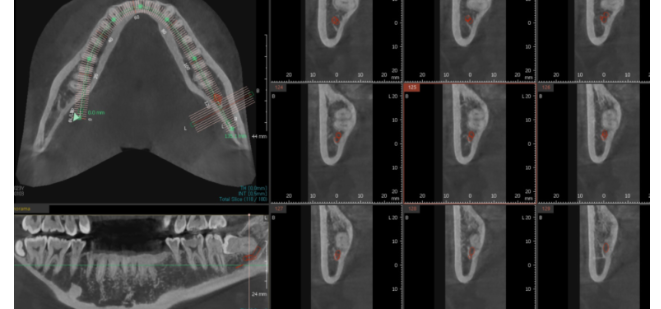

바르디 치과에서는 최신 3d ct 장비가 있어서

사랑니와 신경과의 위치를 파악할 수 있는데요.

사랑니 주변 앞뒤좌우로 발치 시 위험한 요소가 있는지 확인

파노라마 상에서는 붙어있는것처럼 보여도

ct에서는 떨어져있는 경우도 많습니다.

신경관과 사랑니가 떨어져 있는것을 확인

발치가 가능하다 말씀드렸습니다.